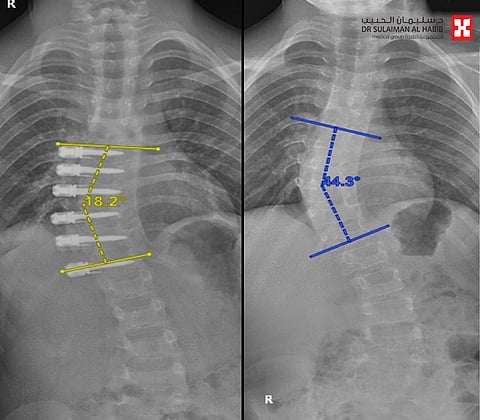

وكان الطفل الذي يعاني أيضًا من التوحد قد راجع المستشفى برفقة ذويه، بعد أن لاحظت الأم مَيَلان عموده الفقري بشكل لافت، وخضع لعدة فحوصات دقيقة؛ لا سيما صور الأشعة السينية والمغناطيسية؛ لتحديد درجة الانحراف والتأكد من خلو الحبل الشوكي من التشوهات والعيوب التي قد تكون مسؤولة عن الخلل الصحي المسبب للميلان.. وأظهرت النتائج وجود انحراف بدرجة 45 بالعمود الفقري، وأكدت سلامة الحبل الشوكي من التشوهات.

وقال رئيس الفريق الطبي المعالج د.سلطان السالمي إنه مع إصابة الطفل بالتوحد تَعَذر التعامل مع حالته بالدعامات والحزام الطبي؛ فضلًا عن أن تزايد درجة الانحراف ووصولها إلى 45 وكون المريض ما زال في مرحلة النمو؛ دفعت الفريق الطبي إلى البحث عن خطة علاجية تستصحب كل هذه المعطيات، وبالفعل أُخضِع المريض لعملية متقدمة تسمى بـ"شد العمود الفقري"، وجرت باستخدام المنظار بمساعدة الدكتور زياد الغامدي من جراحة الصدر، وكذلك استخدام جهاز الملاحة العصبية وتخطيط الأعصاب، وتم فيها تعديل درجة الانحراف باستخدام مسامير وحبل جانبي، مع الإبقاء على مرونة العمود الفقري؛ بهدف توجيه وتقويم النمو ليتم التعديل بشكل تلقائي، وتُعَد العملية الأولى من نوعها بالشرق الأوسط.

ووصف د.وليد البوعلي المدير الطبي للمستشفى التدخل الطبي بأنه يمثل نقلة كبيرة في عمليات تعديل انحرافات العمود الفقري؛ مشيرًا إلى أنها تمت بـ4 فتحات صغيرة لم يتجاوز طولها 2 سم؛ على عكس العمليات التقليدية التي تحتاج إلى فتحات كبيرة وتُلحق الكثير من الضرر بالأنسجة والأعصاب وتتطلب فترات استشفاء طويلة؛ مضيفًا أن العملية التي استمرت لنحو 4 ساعات، تكللت -ولله الحمد- بنجاح كبير؛ حيث غادر المريض بصحة جيدة المستشفى بعد 3 أيام.. ووفقًا للفحوصات اللاحقة للعملية؛ فإن حالته تتحسن باضطراد.